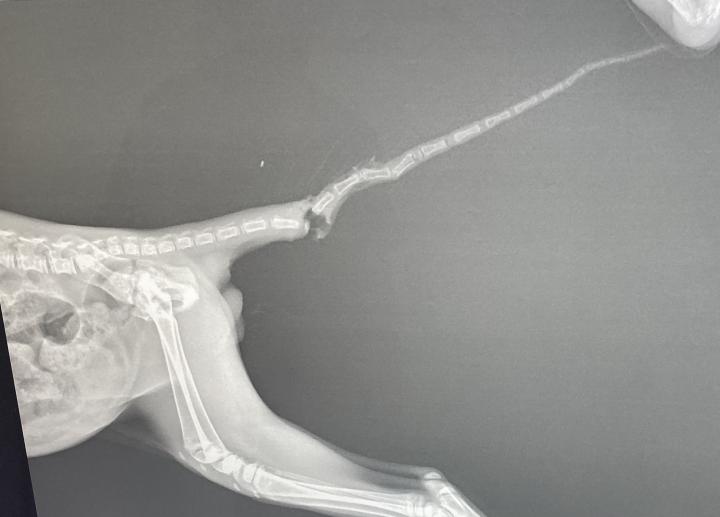

先日拾った体を怪我をしていた子猫は、尻尾も怪我していて断尾することになりました。

尻尾を切るなんて大丈夫なのかと心配でしたが、痛いところがなくなったからか術後のほうが元気でした。